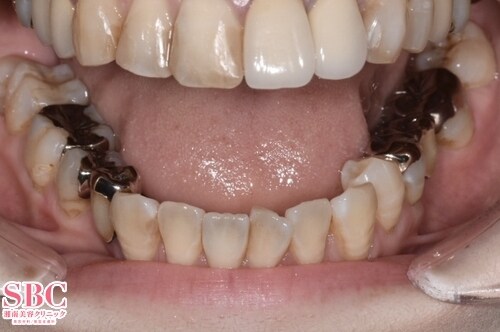

No.318898【美容歯科】の症例写真

施術前

施術後3ヶ月後